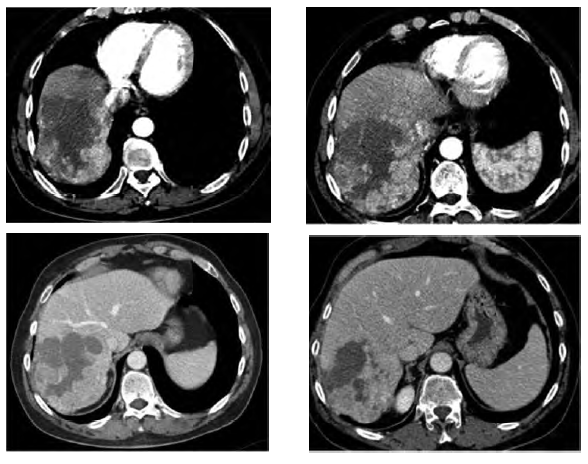

A number of factors have been correlated with effective post-TACE response. These include tumor diameter < 5 cm, < 50% replacement of liver by tumor tissue, and unilobar tumor. Other prognostic factors include the alpha-fetoprotein level, differentiation of HCC, number of tumor nodules, portal vein thrombosis, presence of tumor capsule, and degree of lipiodol retention postprocedure.5,10,15 Drug-eluting beads are microspheres that can be loaded with chemotherapeutic agents and used for TACE. Drug-eluting beads produce controlled, sustained release of chemotherapy at decreased peak plasma levels within the systemic circulation (Figure 3). A randomized clinical trial among 212 patients with intermediate-stage HCC found that TACE with drug-eluting beads resulted in similar response rates to conventional TACE (27% vs 22% complete response and 25% vs 21% partial response) and similar treatment-related serious adverse effects.16

Figure 3. Hypervascular Hepatocellular Carcinoma Lesion in the Right Lobe of Liver